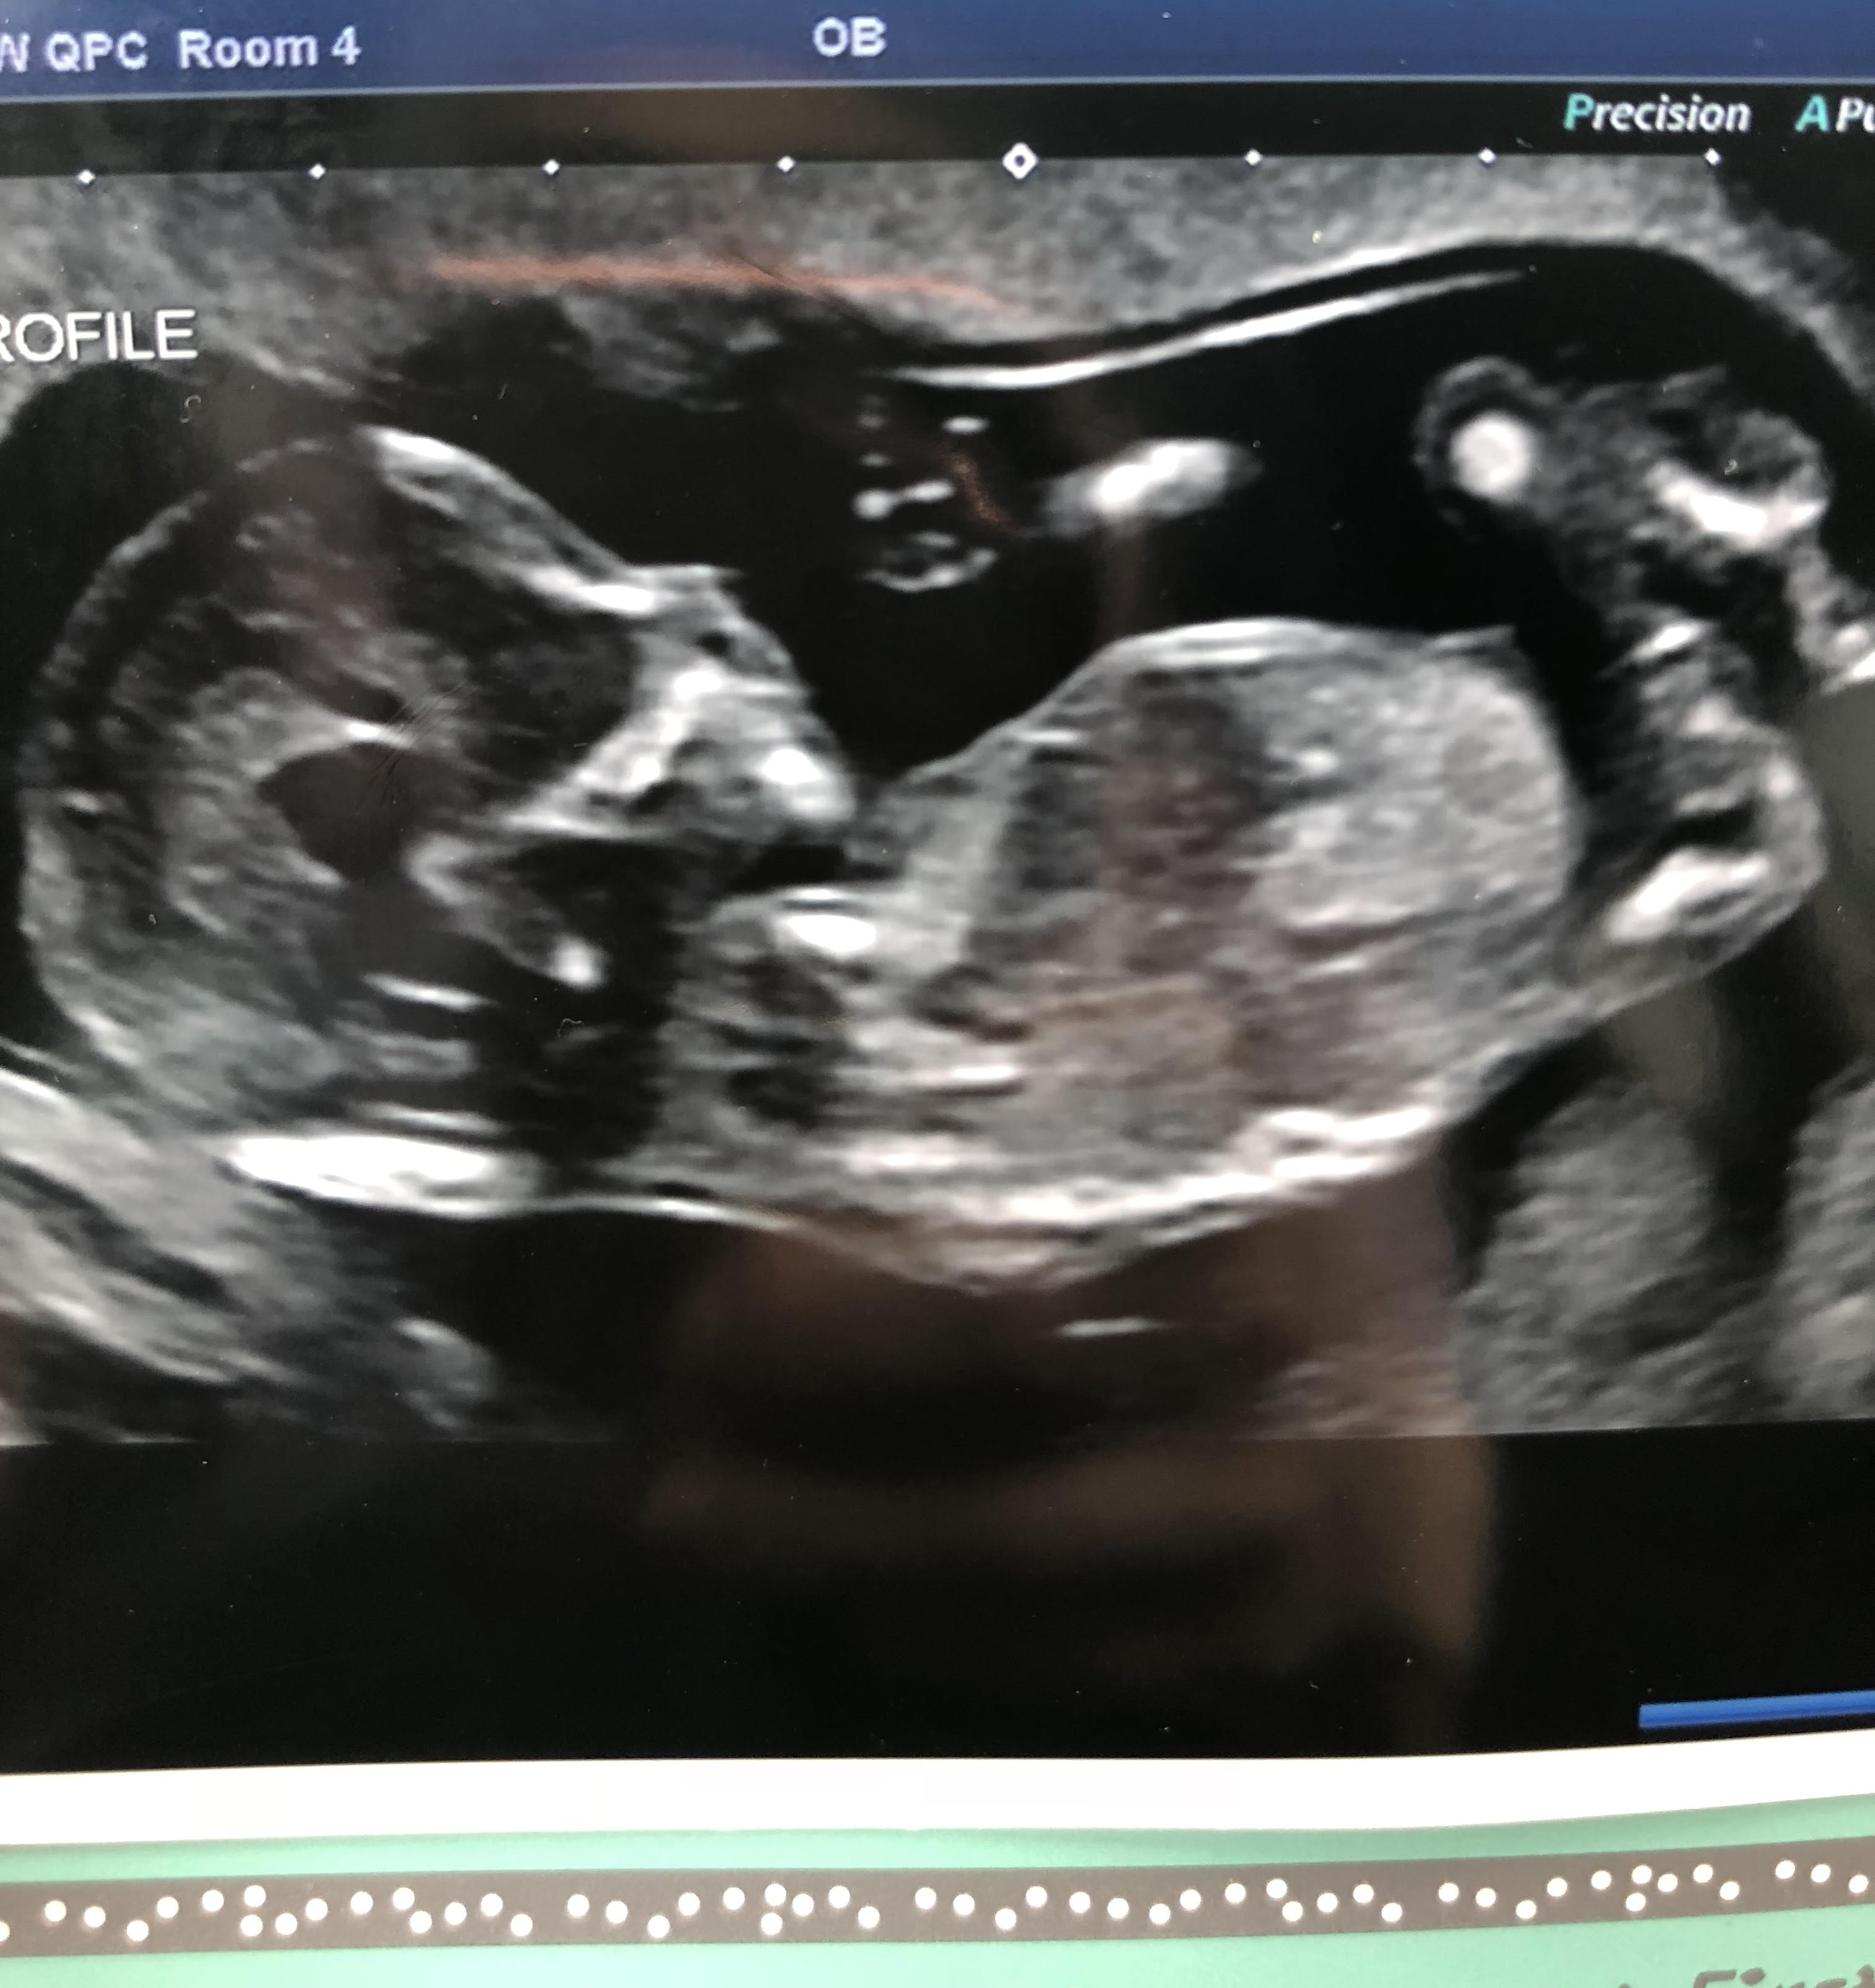

Hi everyone. I went in for a quick 14 week ultrasound today. Baby is sitting at a beautiful heart rate and got to see it’s precious little kicks and squirms. I’m absolutely no good with the nub theory. Is it visible at all in my scan photo? Is it looking like a boy or girly nub? Any guess from those who know how to interpret it are welcome! I will post the photo below. I appreciate your input guys!